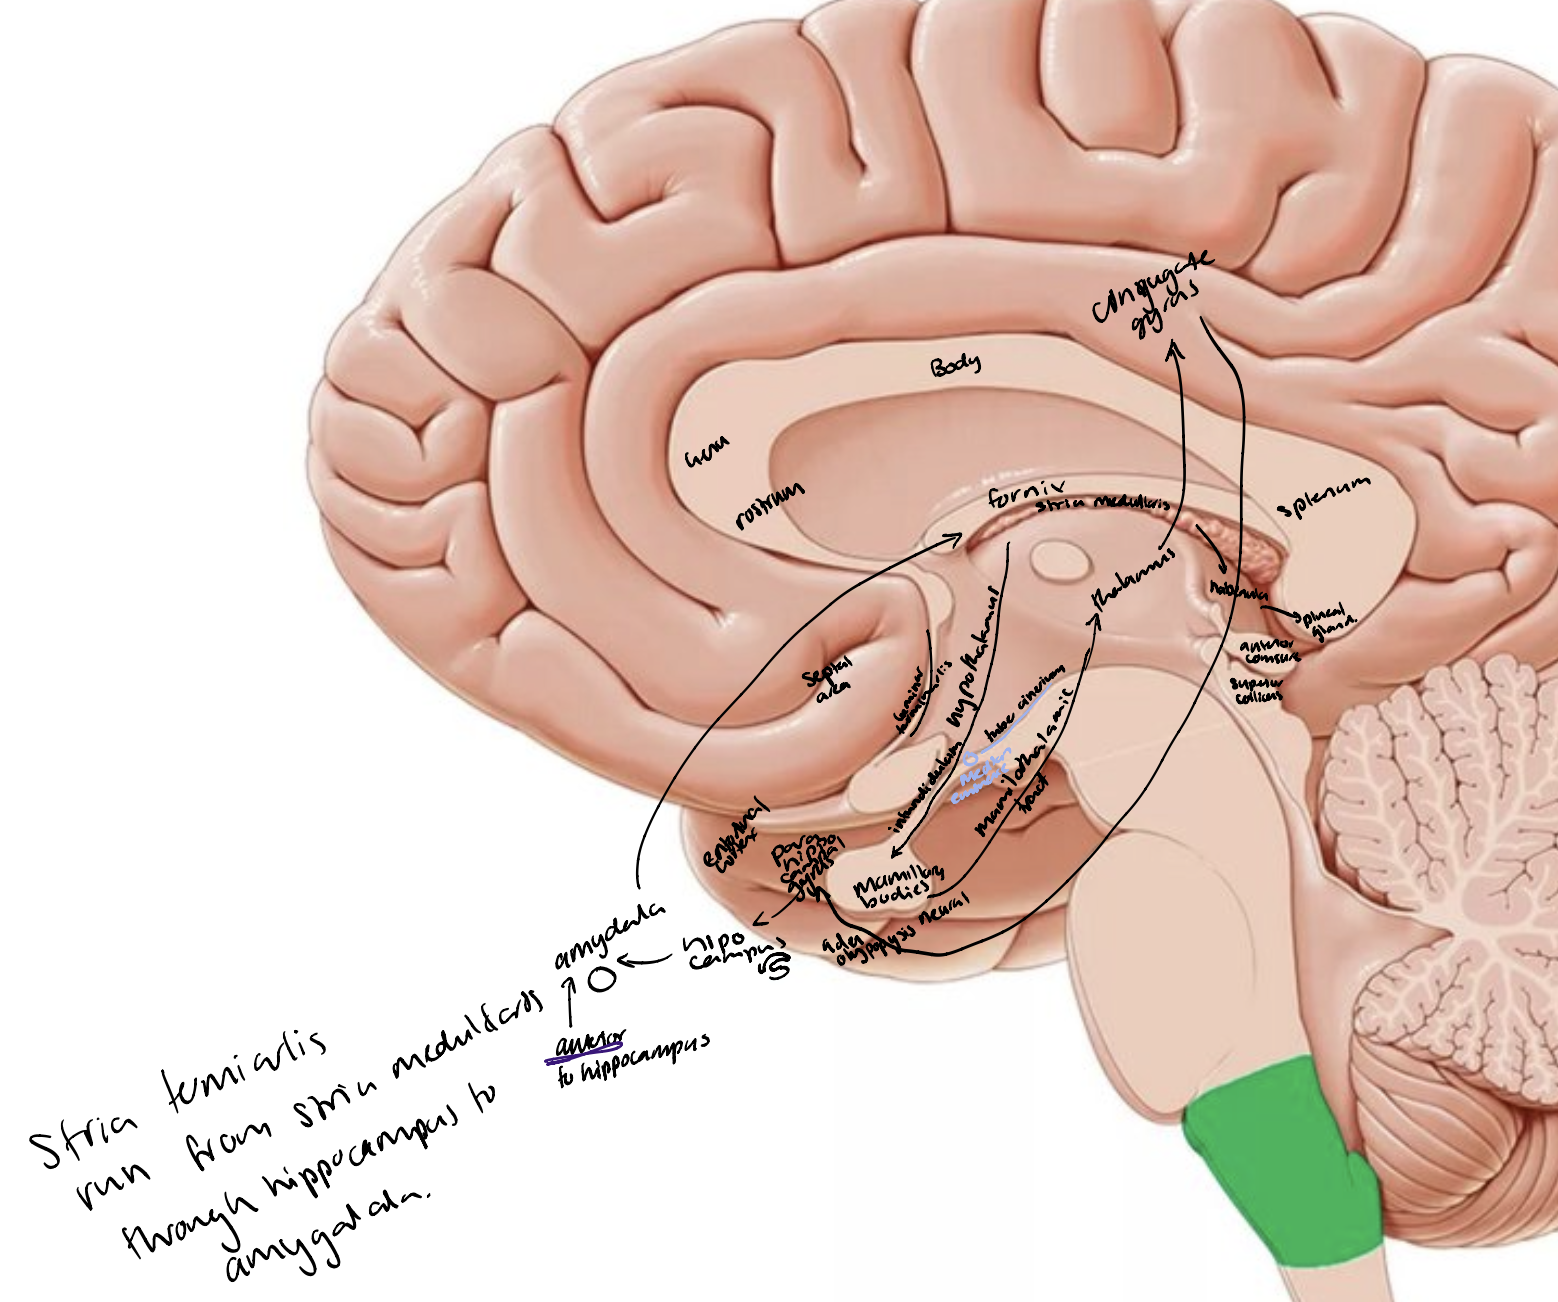

The limbic lobe

Cingulate gyrus

Parahippocampal gyrus (includes entorhinal cortex)

Hippocampal formation in the parahippocampal gyrus

Dentate gyrus

Subiculum

Septal nuclei in the septal area

Amygdala

Nucleus accumbens

Fibre tracts

Fornix

Mammillothalamic tract

Stria terminalis

Stria medullaris thalami

Other parts of the brain e.g., mammillary bodies (hypothalamus), nuclei in the thalamus, rhinencephalon (olfactory bulb, tract, striae.

The Papez Circuit

Parahippocampal gyrus → hippocampus → fimbriae → fornix → mammillary bodies (hypothalamus) → mammillothalamic tract → nuclei of thalamus → cingulate gyrus → parahippocampal gyrus/entorhinal cortex

Hypothalamus

Anterior commissure

Lamina terminalis

Thalamus

Optic chiasm

Infundibulum and pituitary gland

Tuber cinereum

Mammillary bodies

Cingulate gyrus

Fornix

Striae medullaris thalami

Pineal gland

Posterior commissure